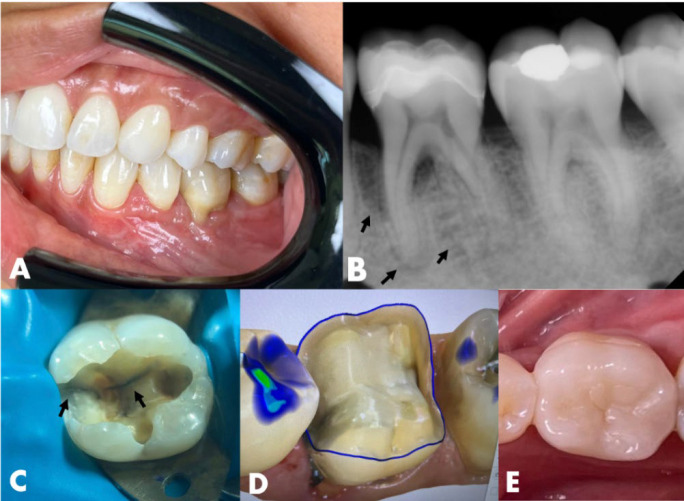

本病例报告强调了Biodentine作为一种孔内屏障的创新应用,用于治疗牙周内病变伴牙根延伸的牙裂。一名37岁女性患者报告咀嚼第36颗牙齿时疼痛。中牙根周围有明显的牙周附着物丧失。牙齿被诊断为牙髓坏死。在根管通道上,观察到一个垂直的裂缝延伸到中管壁。使用旋转器械确定和塑造根管。放置氢氧化钙作为管内敷料。一周后,患者无炎症症状返回。根管内填充了杜仲胶和生物陶瓷水泥。在孔口外2.0 mm处应用生物牙牙素修复水泥来密封和加固该区域。采用复合树脂修复根管通道腔。12个月的临床和影像学随访显示明显的根尖周愈合和无炎症体征。48个月的x线摄影和计算机断层扫描证实了骨修复和牙齿功能的持续。Biodentine的孔内屏障显示出显著的有效性,与文献中关于其益处的报道一致。该方案结合现代技术和及时修复,在处理牙根延伸的牙裂,加强复杂病例的牙齿保存方面显示出希望。

This case report highlights the innovative application of Biodentine as an intraorifice barrier in the management of cracked teeth with radicular extension associated with endo-periodontal lesions. A 37-year-old female patient reported pain during chewing on tooth #36. Significant periodontal attachment loss was noted around the mesial root. The tooth was diagnosed with pulp necrosis. Upon endodontic access, a vertical crack extending into the mesial canal walls was observed. Root canals were identified and shaped using rotary instruments. Calcium hydroxide was placed as an intracanal dressing. After one week, the patient returned without inflammatory signs. The root canals were filled with gutta-percha and bioceramic cement. Biodentine repair cement was applied 2.0 mm beyond the orifice to seal and reinforce the area. The endodontic access cavity was restored with composite resin. Clinical and radiographic follow-ups at 12 months revealed significant periapical healing and the absence of inflammatory signs. A radiographic and computed tomography scan at 48 months confirmed substantial bone repair and continued tooth functionality. The intraorifice barrier with Biodentine demonstrated notable effectiveness, aligning with literature on its benefits. The protocol, integrating modern techniques and timely restoration, shows promise in managing cracked teeth with root extension, enhancing tooth preservation in complex cases.